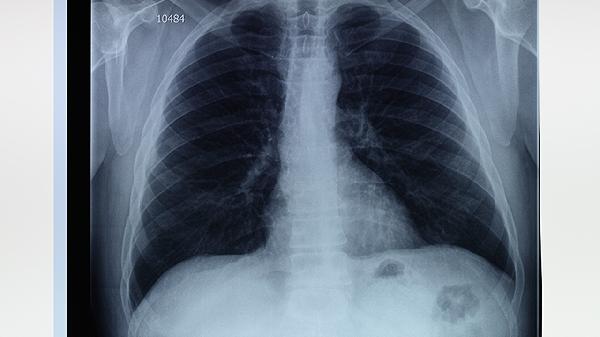

肺楔形切除术后会留下后遗症吗

肺楔形切除术后可能出现短期或长期后遗症,常见情况包括术后疼痛、肺功能下降、胸腔积液、切口感染及慢性咳嗽。术后恢复情况与切除范围、基础肺功能及术后护理密切相关。

术后三个月内应避免剧烈运动及重体力劳动,饮食注重高蛋白、高维生素摄入以促进组织修复,推荐清蒸鱼、鸡蛋羹等易消化食物。每日进行深呼吸练习(每次10分钟,每日3次)可预防肺不张,定期复查胸部CT监测肺复张情况。出现持续发热、咯血或进行性呼吸困难需立即返院评估。